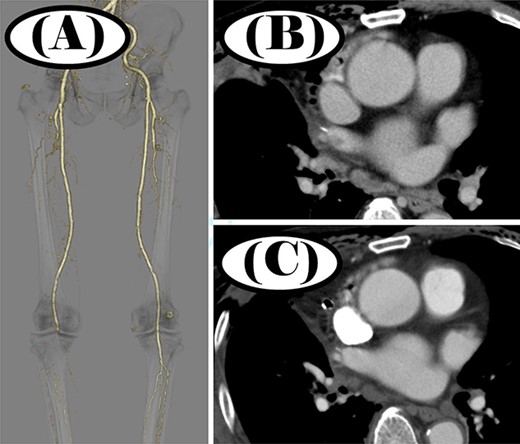

On post-operative day 7, the patient developed right lower extremity coldness as well as pain. Contrast-enhanced CT showed a thrombus in the right superior PVS (Fig. 2B). No vessels were depicted peripherally from the right popliteal artery (Fig. 2A). We diagnosed the patient with acute arterial occlusion of the right lower extremity. Emergency thrombectomy was performed and the patient’s symptoms quickly improved.

Contrast-enhanced CT before and after thrombectomy; (A) no peripheral vessels were depicted beyond the right popliteal artery before thrombectomy; (B) thrombus was seen in the right superior PVS before thrombectomy; (C) thrombus disappeared in the right superior PVS after thrombectomy.

After the thrombus was removed, the patient was started on oral clopidogrel (75 mg/day) and edoxaban (30 mg/day). One week later, a chest CT scan showed resolution of the thrombosis in the right superior pulmonary vein (Fig. 2C). He was discharged from the hospital 3 weeks after the surgery. Five years post-operatively, the patient has shown no signs of recurrence.